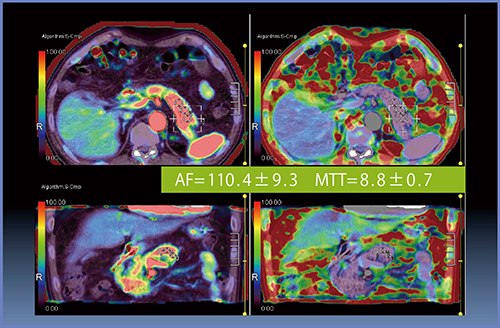

症例1は,下部胆管がんでsoft pancreasの症例である(図3)。Perfusion解析では,AF=110.4±9.3mL/min/100mL,MTT=8.8±0.7sとなっている(図4)。本症例では,術後10日目に膵液瘻による膵液貯留が認められ,CTガイド下ドレナージを施行し,Grade Bと判定された。

図4 症例1のPerfusion解析